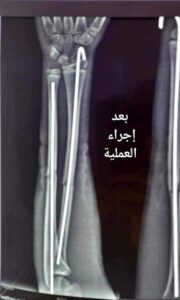

أجرى فريق طبي متخصص بجراحة العظام والكسور في مستشفى الطارمية العام التابع لدائرة صحة بغداد الكرخ برئاسة الدكتور أحمد فاضل عملية لتعديل كسر في الذراع لفتى بعمر (13) عام يعاني من ألم شديد مع تورم في منطقة الزند ومنطقة الكعبرة في الذراع واجريت له كافة الفحوصات الطبية اللازمة وادخل المريض الى صالة العمليات وتكللت العملية بالنجاح حيث تم تعديل الكسر باستخدام الشيش الداخلي والمريض بحالة صحية ج

يدة.